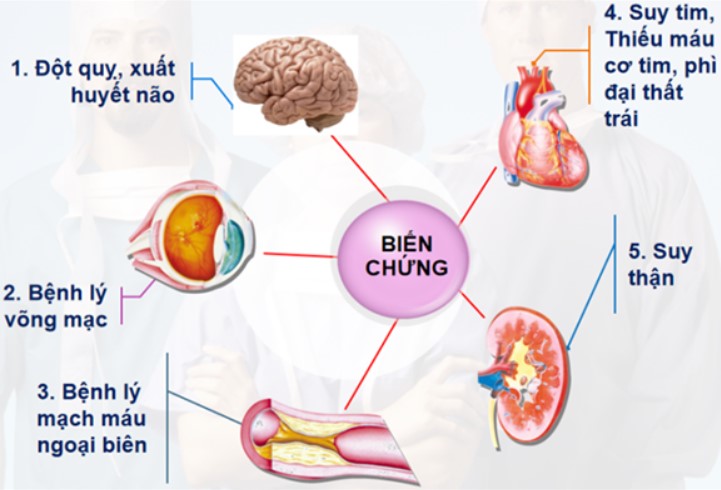

Nguyên nhân khiến người bị tiểu đường dễ đột quỵ não

Đái tháo đường là căn bệnh không lây nhiễm nhưng để lại biến chứng nặng nề. Trên thế giới có 415 triệu người bị tiểu đường, tức là cứ 11 người sẽ có 1 người bị đái tháo đường. Bệnh được ví như sát thủ nguy hiểm, một trong những nguyên nhân gây tử vong hàng đầu thế giới.